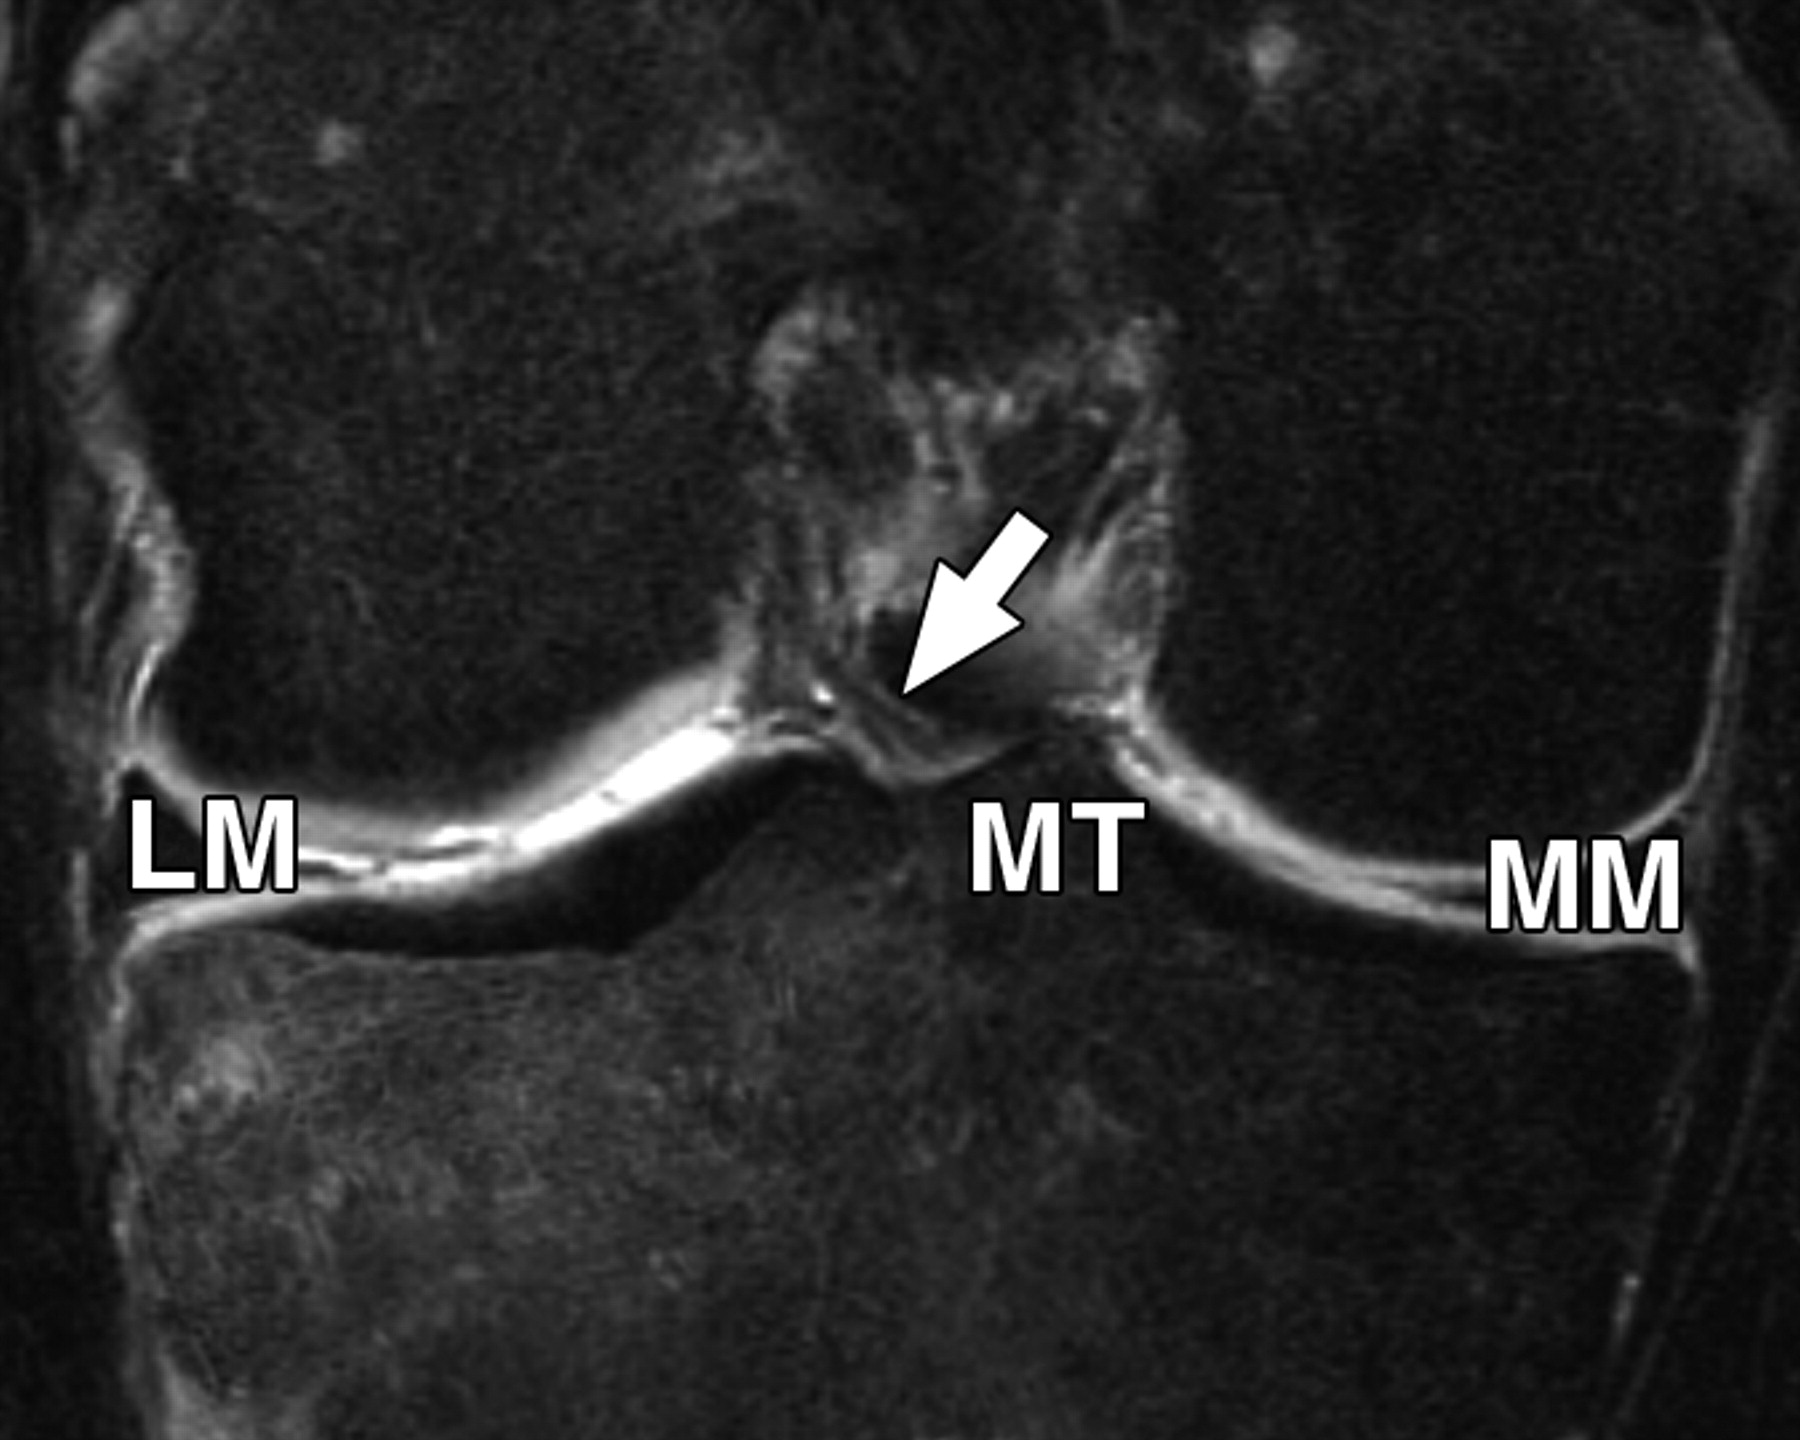

图5C-59岁男性,中等加权、脂肪饱和、快速自旋回波(TR/TE有效值,3,700/29)3-T MR图像显示半月板后根和交叉韧带的解剖关系。

冠状面图像依次位于A的腹侧,显示外侧半月板后根(LM)(白色箭头)和内侧半月板后根(MM)(黑色箭头,B)的插入,覆盖后髁间区域的一个以上切片厚度。MT =胫骨内侧结节。

图5D-59岁男性,中等加权、脂肪饱和、涡轮自旋回波(TR/TE eff,3,700/29)3-T MR图像显示半月板后根和交叉韧带的解剖关系。

通过后交叉韧带(P)的矢状图像显示内侧半月板后根的插入部位(箭头)相对于韧带插入部位位于前方。MT =胫骨内侧结节。箭头表示膝前韧带。